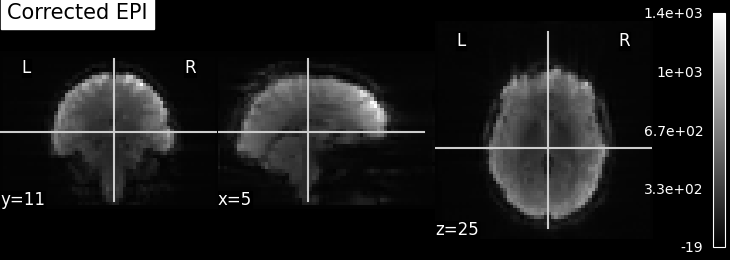

EPI field mapping

EPI images can be utilized to approximate a field map by acquiring two volumes with opposite phase encoding directions. The difference in distortion between these two acquisitions is then utilized in a least squares algorithm to estimate the field map. Although the resulting field map may exhibit some artifacts, as demonstrated in the following images, it is still sufficient to correct for distortion to some extent.

To perform this step, FSL command line tools such as TOPUP, FUGUE, and FLIRT are employed for the analysis. These tools enable the processing and correction of distortion in the EPI images, contributing to improved image quality.